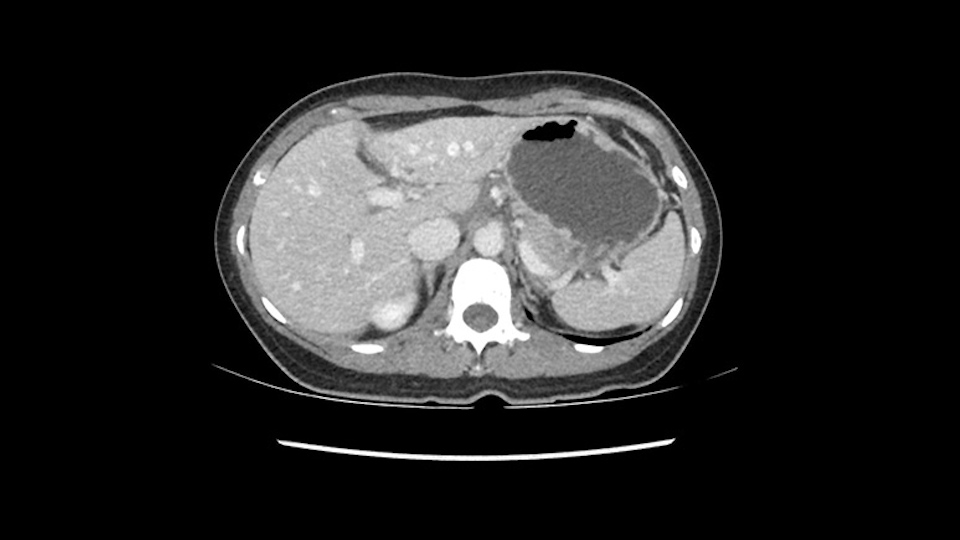

So if we look at the CT scan, on the axial, it’s a larger lesion. It’s about 6 or 7 or 8 centimeters. So it does look a bit threatening in terms of its resectability but if you really drill down deeply into the anatomy, and I think the coronal [imaging] is even better, you can see that the entire mass is on the patient’s left side of the falciform ligament. So it’s really only a left-sided tumor and not even really a left-sided tumor because Segment 4 is uninvolved anatomically.

When you see the axial sections of the scan, you find it's a largely exophytic mass and its well-encapsulated. So this is typically true of a well-differentiated hepatocellular carcinoma. If you look at this, this is the gallbladder which is being displaced to the right and the mass is in the Sg4 of the liver, exophytic, projecting down. As it is coming down, it is also displacing the duodenum and the head of the pancreas which is being pushed towards the left and it's going right up to the cava, the start of the anterior surface of the cava. Obviously getting a lot of collaterals and vascularity from all the vessels around but one has to be very careful in evaluation of the main portal pedicle in this particular case and of course arterial inflow to the Sg4 and of course the left lobe of the liver.

What kind of procedure can we plan for this patient? It obviously has to be a left hemihepatectomy because most of the lesion is actually in Sg4. Can we do something which is less than a hemihepatectomy and just do only a segmental resection? The answer to that is that this vascular supply, if you are trying to ligate only the portal venous pedicle to the Segment 4, it is very close to the tumor and you will end up not having not a great margin as far as tumor resection is concerned so I would recommend a left hemihepatectomy and not just a partial or segmental resection. You can also see that it is crossing the falciform line and going on to Segment 2 and 3 so trying to do anything less than a left hemihepatectomy may not give the right kind of margins which we need for this tumor. Fortunately for us, the contours of the liver, which are very important to see in a Hepatitis B patient, there are no cirrhosis which I can see. The normal liver functions indicate that it's a well compensated Hepatitis B.

So in planning for this operation, as I look at the scans, I first visualize the arterial phase and I can see that there’s are a lot of big feeding arteries to this large tumor. Likely all the right side vessels feeding the right side of the liver: right hepatic artery and likely the Segment 4 artery are spared from the tumor. It’s likely the left hepatic artery is ramificating and giving feeding arteries to this tumor. It certainly looks like a large mass that its compressing other structures like the cava, the pancreas, the stomach; but I think there’s a plane and we can see that better in the venous phase. There’s a plane of separation between the gallbladder, the pancreas, the cava, that this tumor is abrupting but likely not invading. Usually, these masses actually don’t invade at that level and basically are pushing the tissues and once you open, you’re able to separate the tumor. Sometimes there’s some adhesions but you can actually separate and there’s usually no invasion.